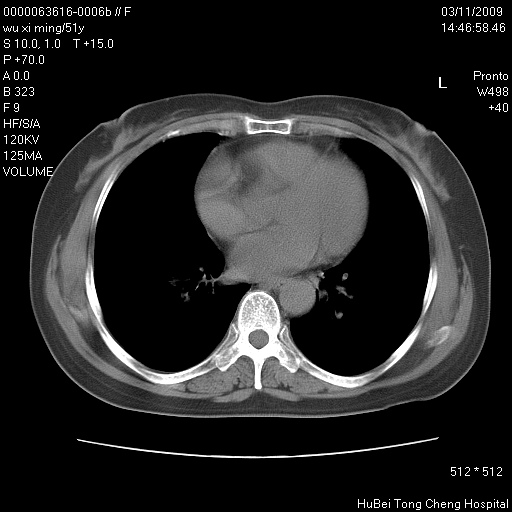

患者 女,51岁。因“胆囊炎,胆囊结石”,行常规术前胸部x线检查发现:右上肺结节病灶,建议行进一步检查。患者无咳嗽、咳痰及咯血等呼吸道症状,近期出现背部疼痛不适。

胸部ct轴位平扫(层厚10mm,螺距1.5,重建间隔10mm;部分层面:层厚3mm,螺距1.0,重建间隔3mm),图像如下:

右肺周围型肺癌伴肺内转移信胸椎转移

有周围性肺癌胸椎转移

右肺周围型肺癌伴肺内转移及胸椎转移。已无手术机会。